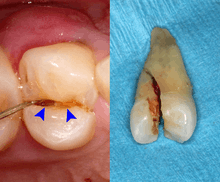

Cracked tooth syndrome refers to a highly variable[29] set of pain-sensitivity symptoms that may accompany a tooth fracture, usually sporadic, sharp pain that occurs during biting or with release of biting pressure,[30] or relieved by releasing pressure on the tooth.[9]:24 The term is falling into disfavor and has given way to the more generalized description of fractures and cracks of the tooth, which allows for the wide variations in signs, symptoms, and prognosis for traumatized teeth. A fracture of a tooth can involve the enamel, dentin, and/or pulp, and can be orientated horizontally or vertically.[9]:24–25 Fractured or cracked teeth can cause pain via several mechanisms, including dentin hypersensitivity, pulpitis (reversible or irreversible), or periodontal pain. Accordingly, there is no single test or combination of symptoms that accurately diagnose a fracture or crack, although when pain can be stimulated by causing separation of the cusps of the tooth, it's highly suggestive of the disorder.[9]:27–31 Vertical fractures can be very difficult to identify because the crack can rarely be probed[9]:27 or seen on radiographs, as the fracture runs in the plane of conventional films (similar to how the split between two adjacent panes of glass is invisible when facing them).[9]:28–9

The prognosis for a cracked tooth varies with the extent of the fracture. Those cracks that are irritating the pulp but do not extend through the pulp chamber can be amenable to stabilizing dental restorations such as a crown or composite resin. Should the fracture extend though the pulp chamber and into the root, the prognosis of the tooth is hopeless.[9]:25